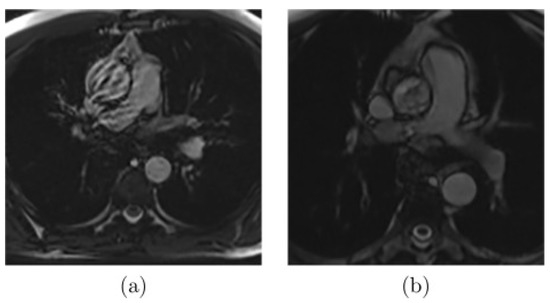

As presented in Figure 2, there are images where noise or artifacts are often present in the critical part of the cardiac cycle, especially for the ascending aorta, as the FLASH sequence is sensitive to rapid and turbulent flow. Another extreme case that complicates the segmentation (Figure 3a) appears when the aortic border is poorly visible due to the proximity of some other structures. Finally, other common difficulties can be encountered, such as the highly dilated ascending aorta as shown in Figure 3b.

Figure 2.

Examples of MR images with artifacts due to (a) rapid or (b) turbulent blood flow [20].

Figure 3.

Examples of MR images where (a) the aortic wall is not well-defined due to the influence of the proximity of other structures or (b) the aorta is highly dilated [20].